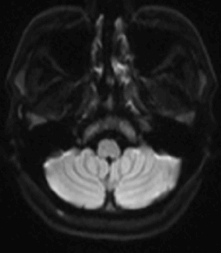

颅脑MR(水抑制)

颅脑MR(DWI)

发病第三日完善了颅脑MR检查:左侧大脑半球脑梗死(病灶新旧不一) 。